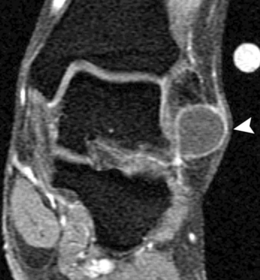

What does this show? | Ganglion in lateral ankle soft tissue |

What does the arrow show? What could this be? | Teardrop-shaped hypointense lesion in third interspace. Could be morton's neuroma |